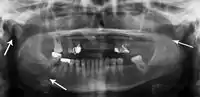

Panoramic radiography

Panoramic radiographs are tomograms where the mandible is in the focal trough and show a flat image of the mandible. Because the curve of the mandible appears in a 2-dimensional image, fractures are easier to spot leading to an accuracy similar to CT except in the condyle region. In addition, broken, missing or malaligned teeth can often be appreciated on a panoramic image which is frequently lost in plain films. Medial/lateral displacement of the fracture segments and especially the condyle are difficult to gauge so the view is sometimes augmented with plain film radiography or computed tomography for more complex mandible fractures.

Panoramic radiograph of a simple mandible fracture of the right mandibular body, minimally displaced. Note that the teeth to the left of the fracture do not touch

lateral oblique image demonstrating a fractured mandible.

Towne's view of a bilateral condyle fracture. White arrow is a fracture on the neck of the condyle. Black arrow shows the condyle pulled to the medial. The same injury can be seen on the opposite side

3D CT reconstruction of mandible fracture, white arrow marks fracture, red arrow marks moderate displacement and open bite

occlusal radiograph of a mandibular parasymphysis fracture